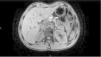

Fifteen-year-old male with blunt abdominal trauma. He presents to the ER at 12h with diffuse abdominal pain unresponsive to the usual analgesic medication. He shows a good state of health; vital signs look good; and the blood tests conducted confirm levels of amylase of 3005U/l (20–100U/l). An abdominal ultrasound scan is conducted that shows the presence of abundant free fluid in the pouch of Douglas which leads to conducting an additional abdominal CT scan with contrast that shows the complete rupture of the pancreatic body (Fig. 1). Initially, the management of the patient is conservative under intensive monitoring at the ICU. A magnetic resonance imaging confirms the aforementioned complete rupture (Fig. 2). Yet despite this fact, conservative management is not withdrawn given the patient's complete and constant stability. After seven (7) days, the progression of the rupture is favorable according to the ultrasound scan and free fluid is completely gone. The patient is discharged from the hospital after eight (8) days with no symptoms or any associated complications.